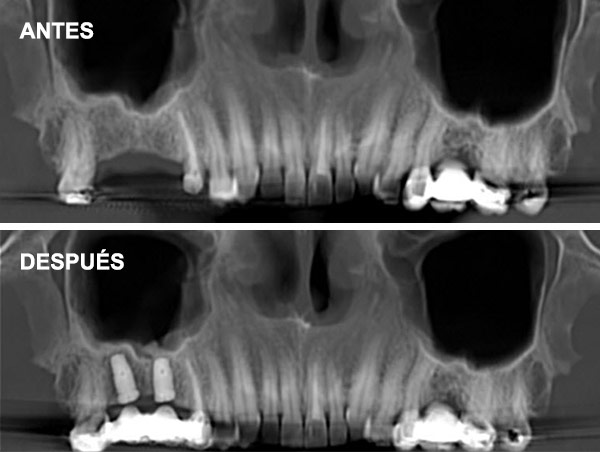

Esta técnica consiste en aumentar la altura y anchura del hueso en los maxilares introduciéndonos en el seno para conseguir una base ósea que permita la colocación de implantes.

Cuando no hay hueso ni distancia suficiente entre el maxilar superior y el seno (altura menor a 5 mm) que imposibilita la colocación de implantes.

Indicaciones: Se emplea en casos donde la cantidad de hueso residual es muy escasa (<5 mm) o cuando se necesita un aumento significativo del volumen óseo.

Permite una visualización directa y control del procedimiento. Útil para grandes reconstrucciones óseas.